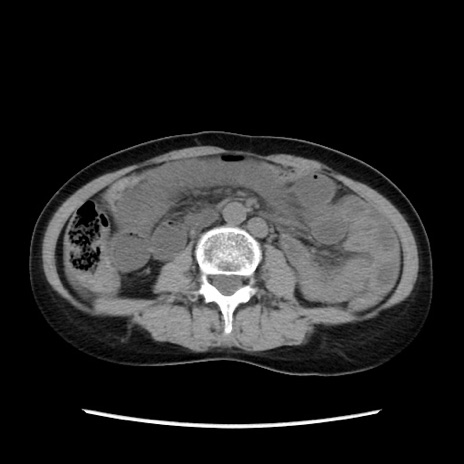

症例32(横断像)

【症例】40歳代 女性

【主訴】上腹部痛、嘔気・嘔吐

【現病歴】約9時間前頃から急に上腹部痛、嘔気、嘔吐が出現。改善しないため救急要請。

【既往歴】子宮頚癌(広汎子宮全摘術、放射線療法)、腸閉塞

【身体所見】腹部:平坦、軟、腸雑音亢進、上腹部を中心に腹部全体に圧痛あり。

【データ】WBC 8400、CRP 0.03